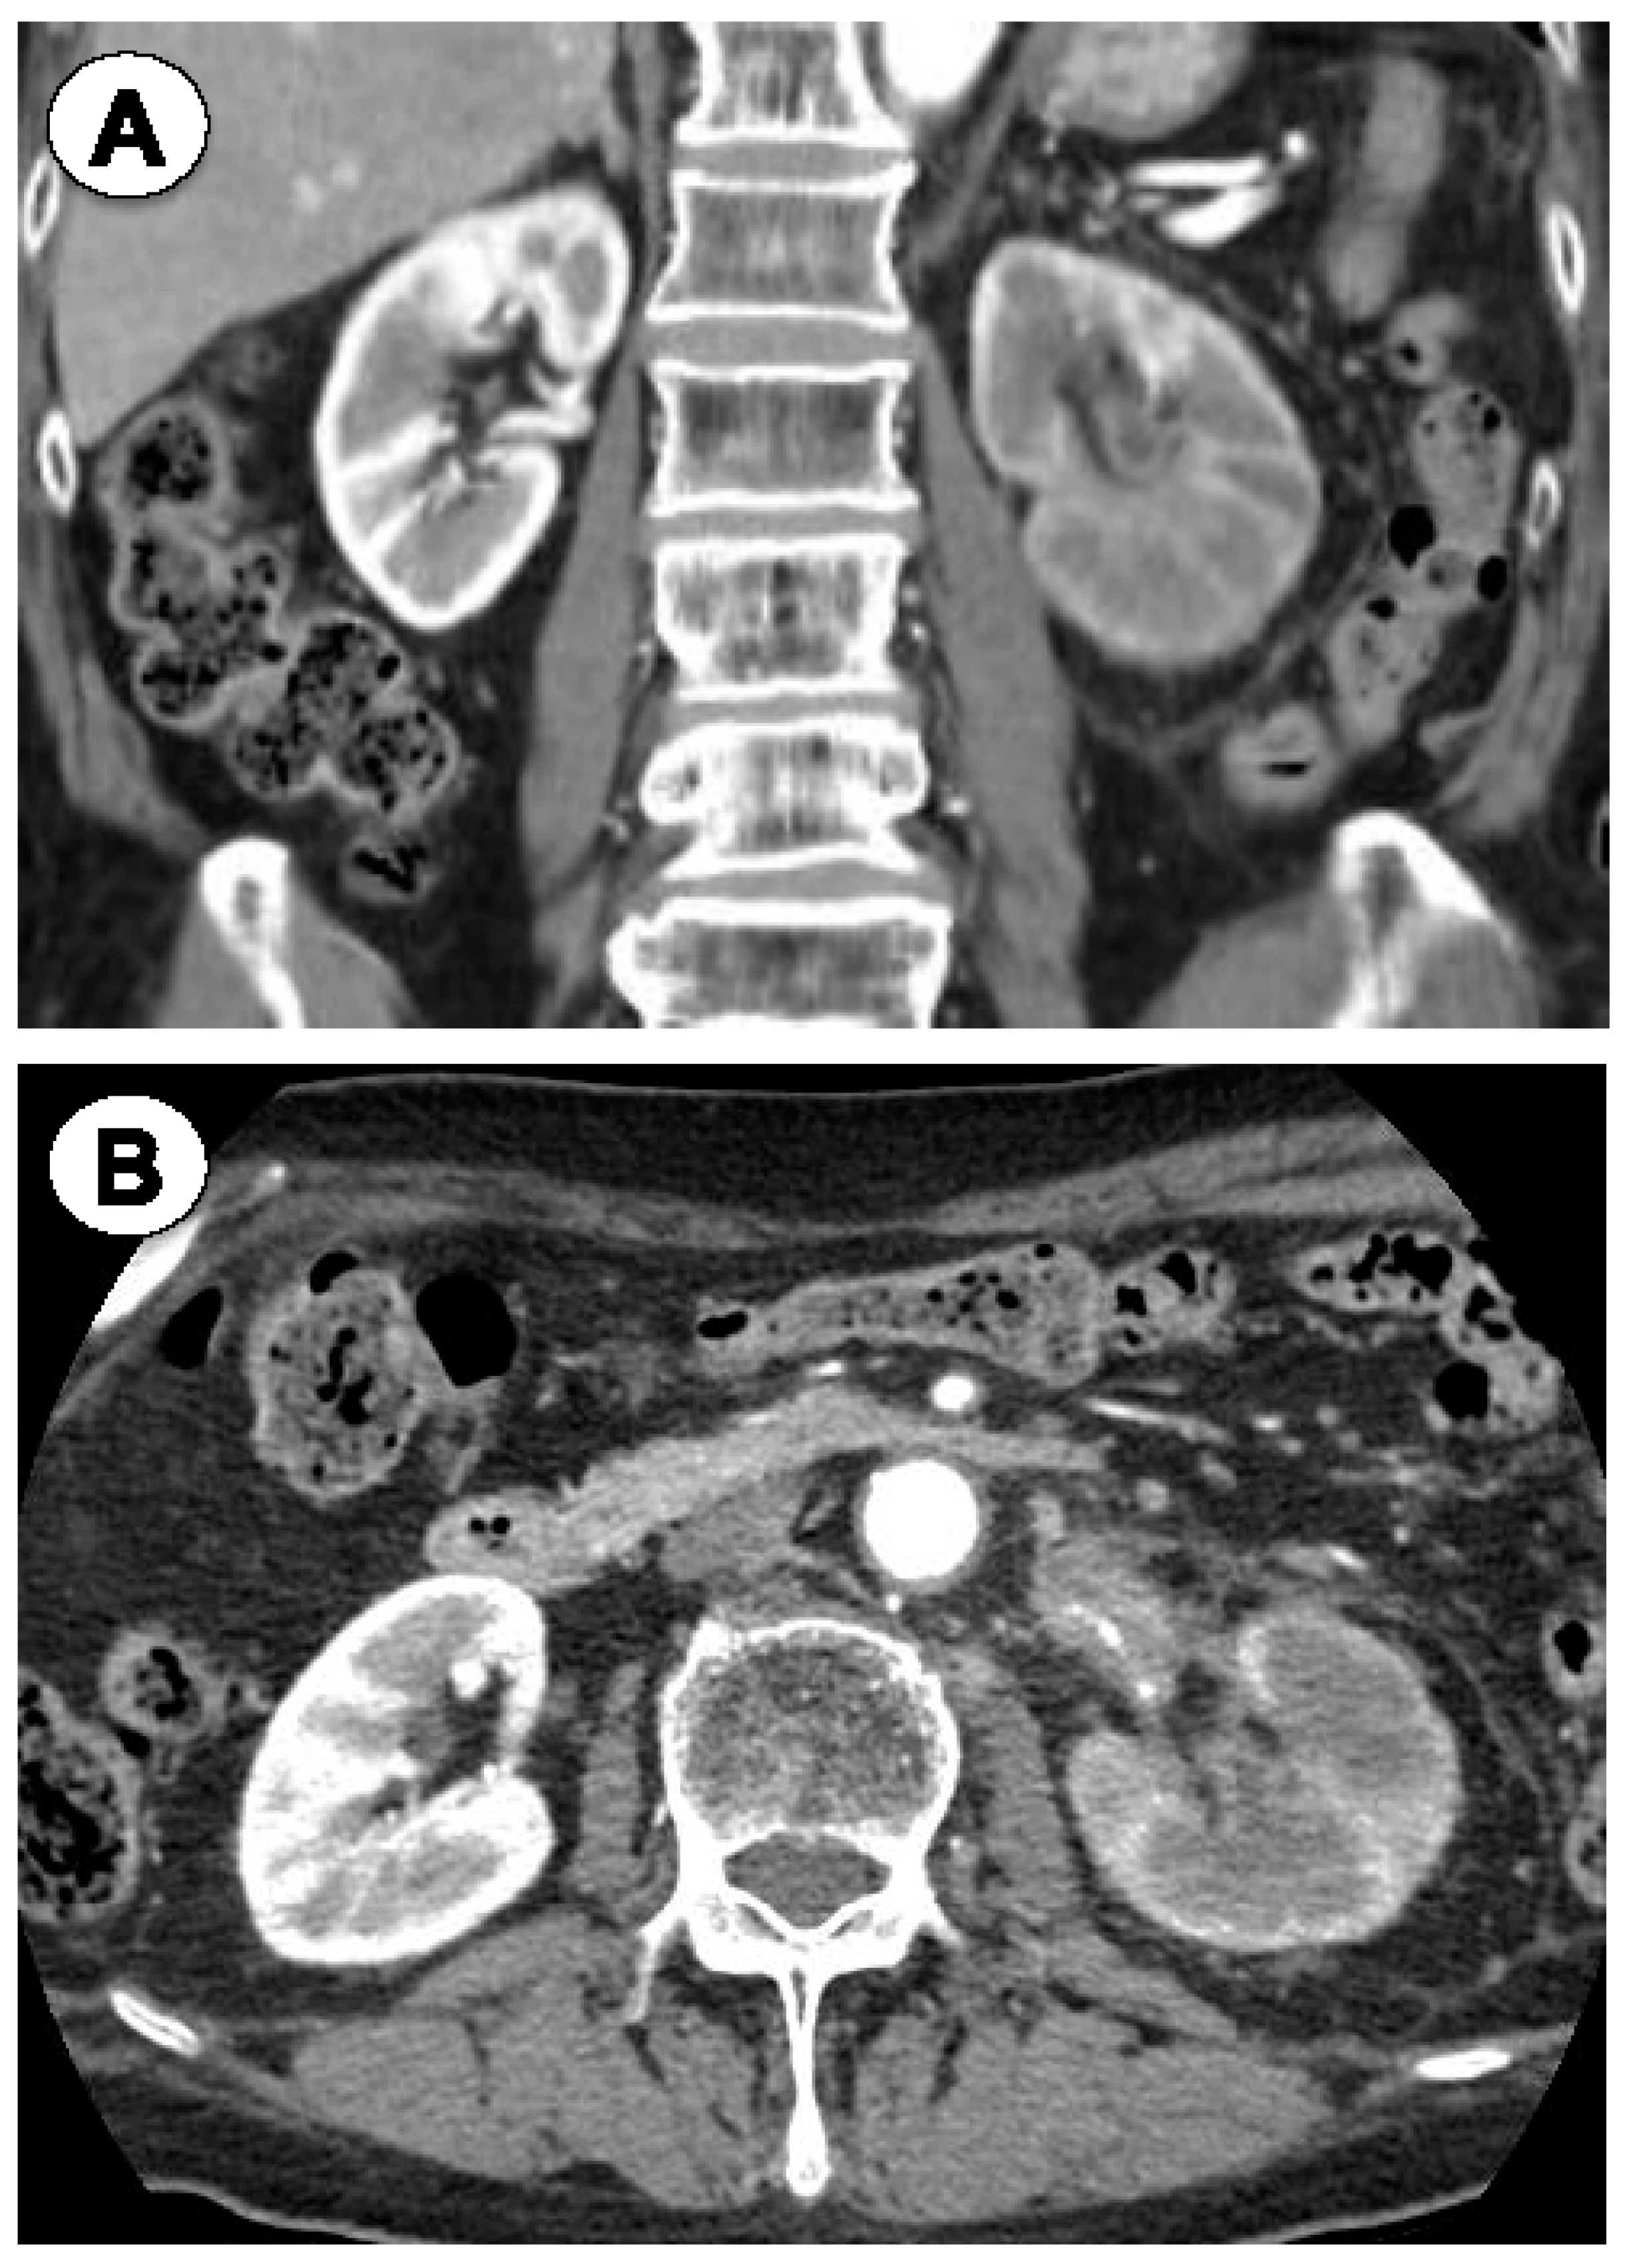

2.1. Case 1

2.2. Case 2

2.3. Case 3